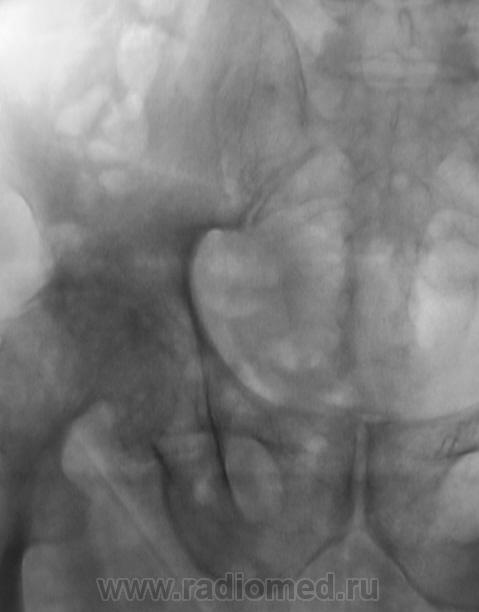

В принципе, болеть есть от чего. Однако, у меня на подозрении очаги разрежения структуры в головке левой бедренной кости и в теле правой подвздошной кости над вертлужной впадиной. Очаги весьма четкие, круглые - дообследуйте на предмет миеломной болезни.

Справа на фоне лонной и седалищной костей по-видимому тени кишки - грыжа?

Бластического варианта НЕТ. Очаги просветления, в данном случае -затемнения газ в к-ке. ДОА пр.т/б сустава 4 , левого - 2 степени, артрозные изм-я в сакроилеальных сочленениях, выраженней в левом

Правая половина таза меньше за счёт проекционного искажения?

Да, положение вынужденное.